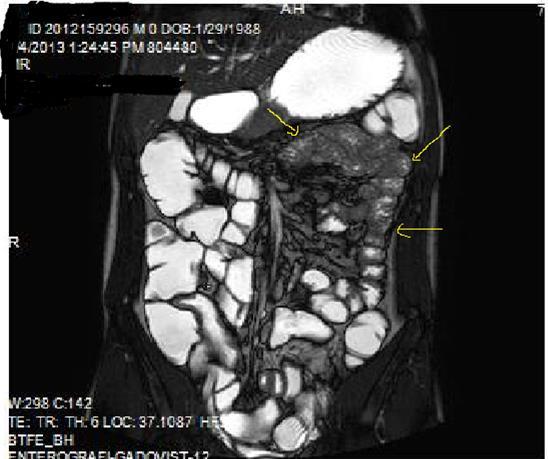

Diffusion-weighted imaging(DWI) and magnetization transfer imaging(MTI) are the new imaging sequences and techniques that can be performed for the accurate diagnosis of Crohn’s disease2, 9, 10. In case of active inflammation, restricted diffusion on high-b-value is conducted at DWI in case of Crohn’s disease, whereas infrequent for ulcerative colitis. To my experience, DWI may play a collaborating role in the imaging of patients who can’t tolerate OCA’s or in patients in whom IV contrast agent use is contraindicated5, 9.MTI may reflect the enteric fibrosis and stricture development in Crohn’s disease via transfer of energy from the free water protons inside the lumen, to the macromolecules especially for the collagen fibers at the bowel wall9, 10, 11, 12. Motility of the small intestine can be visualized by cine MRI via fast T2W images or true fast steady-state precession imaging, abnormal bowel motility and inflammatory activity in Crohn’s disease can be shown, based on wall thickness, ulceration and T2 signal intensity 9, 11, 12, 13 (Figure 1a-b).

Figure 1a.Diffuse mucosal involvement and increased wall thickness with loss of valvula conniventes in the ileal segments on T2W coronal images after OCA administration, seen on 30 years old female with moderate Crohn’s disease.

Figure 1b.Diffuse bowel wall enhancement in the small intestine due to Crohn’s disease on the Post-contrast T1W coronal sequence.